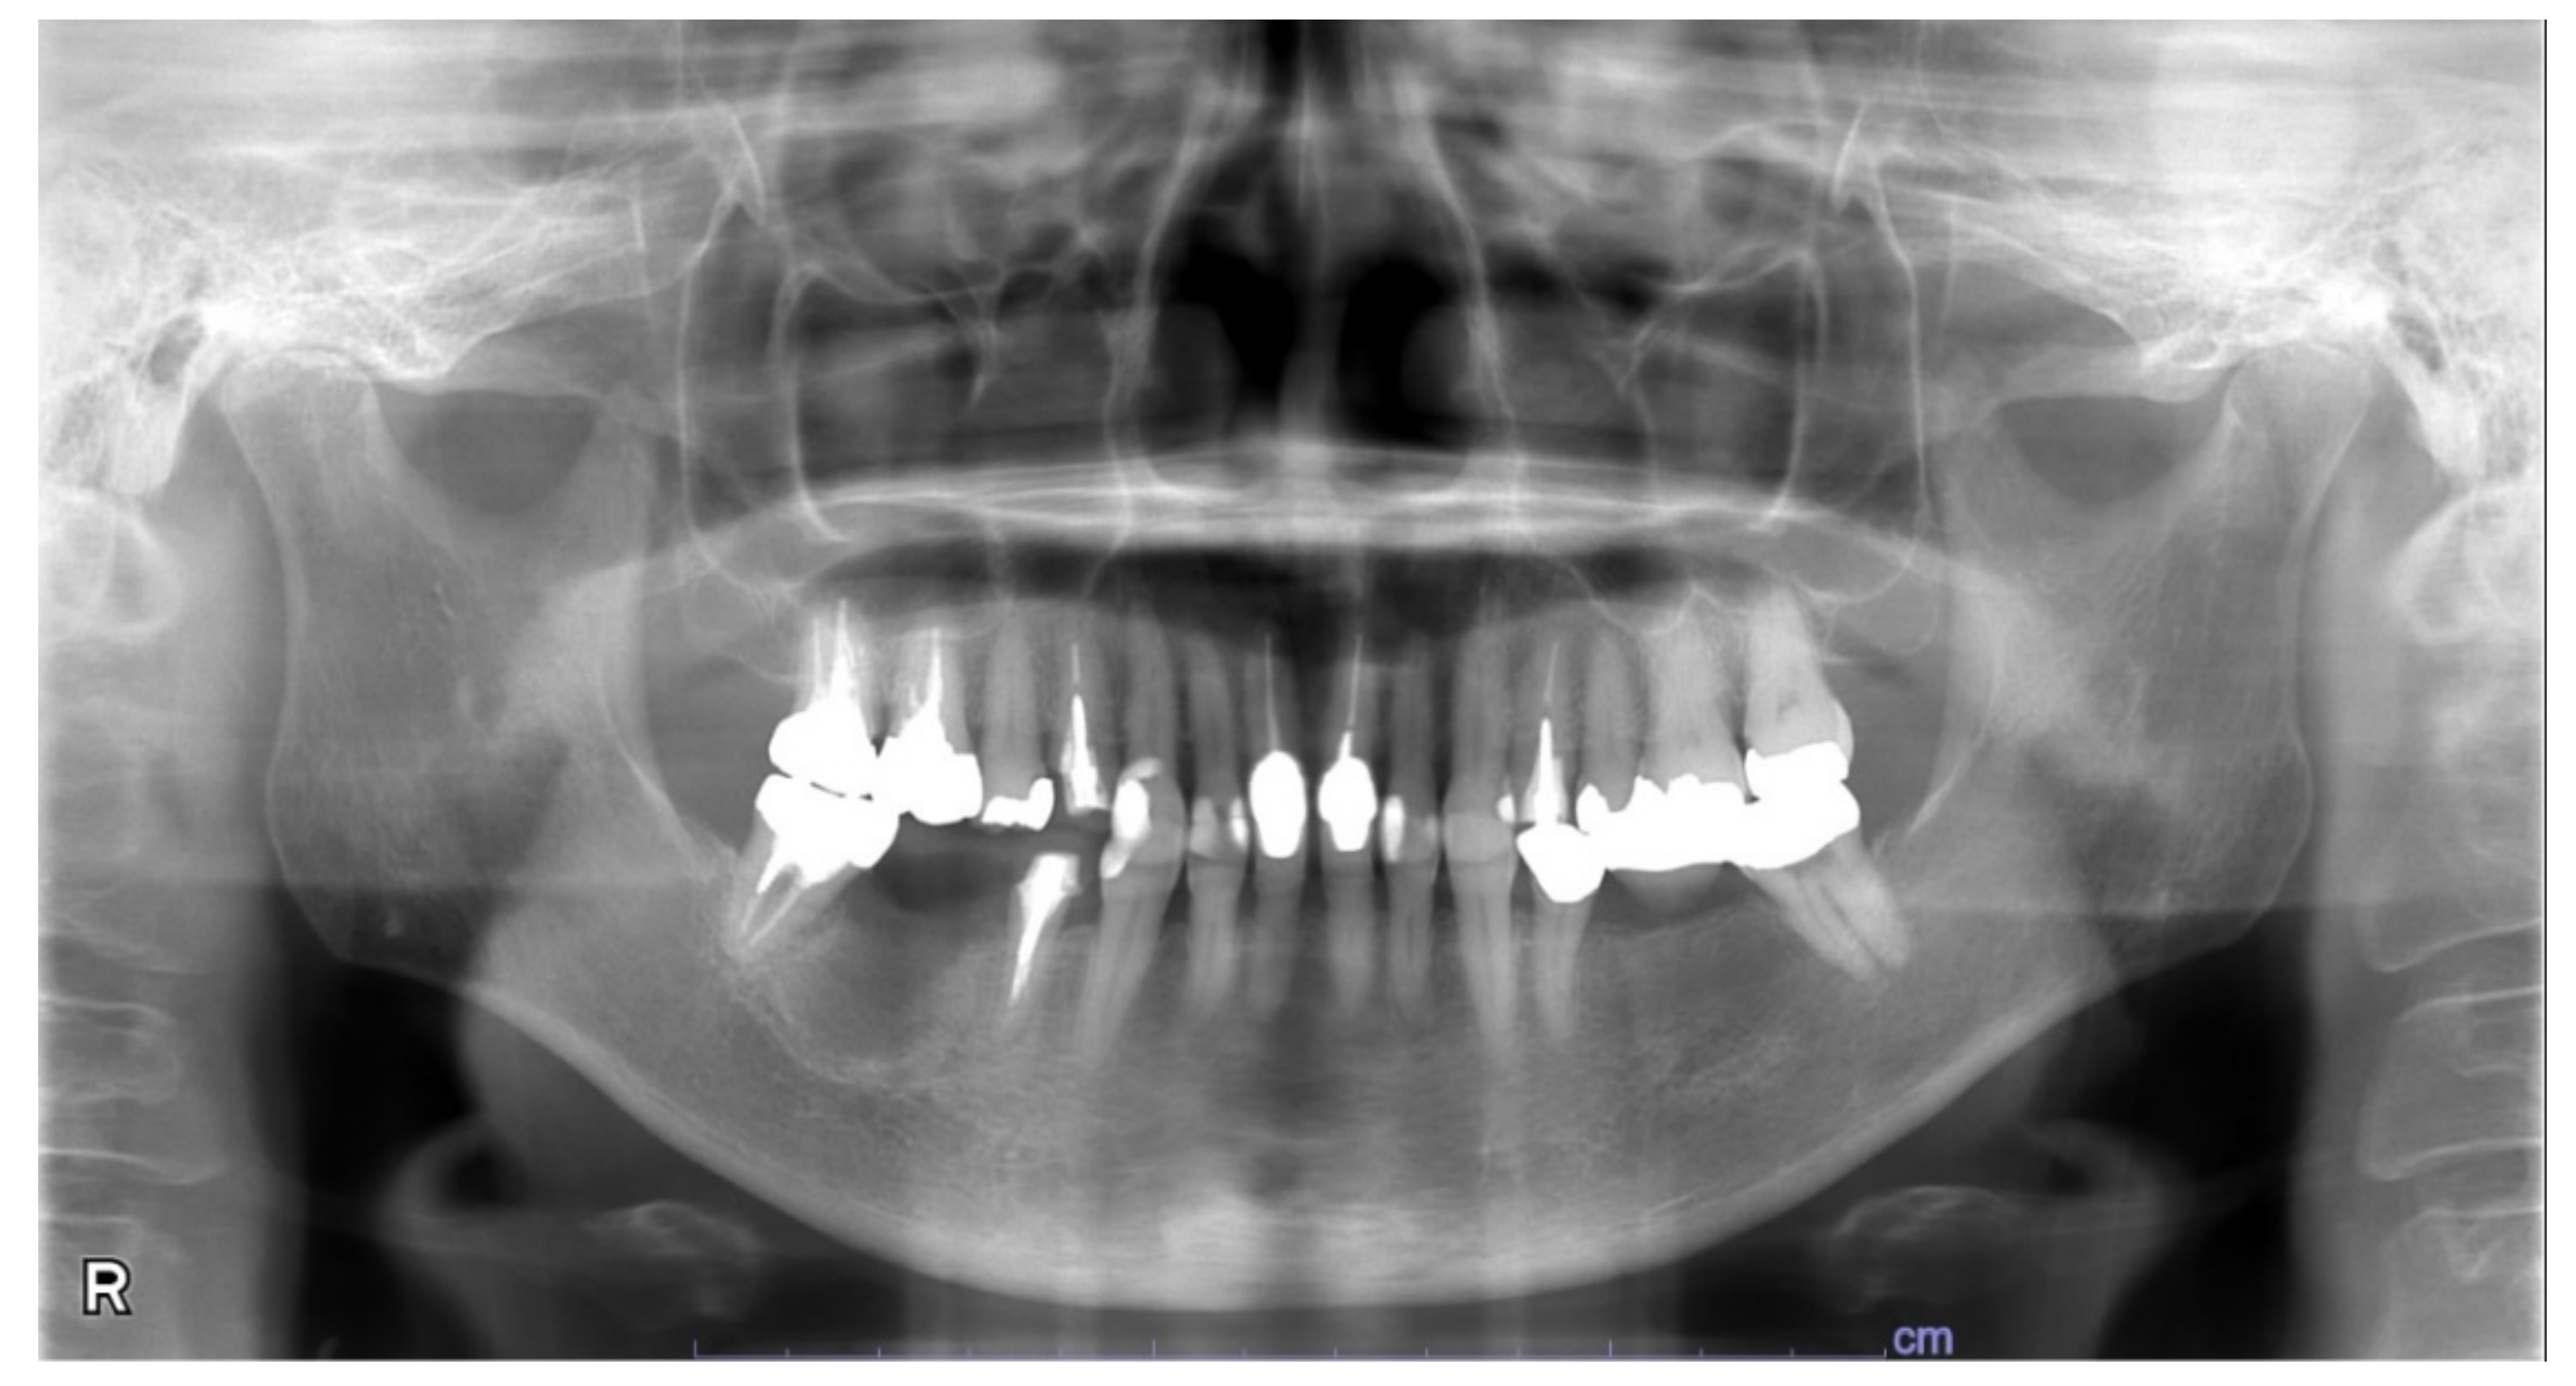

3. Case Report